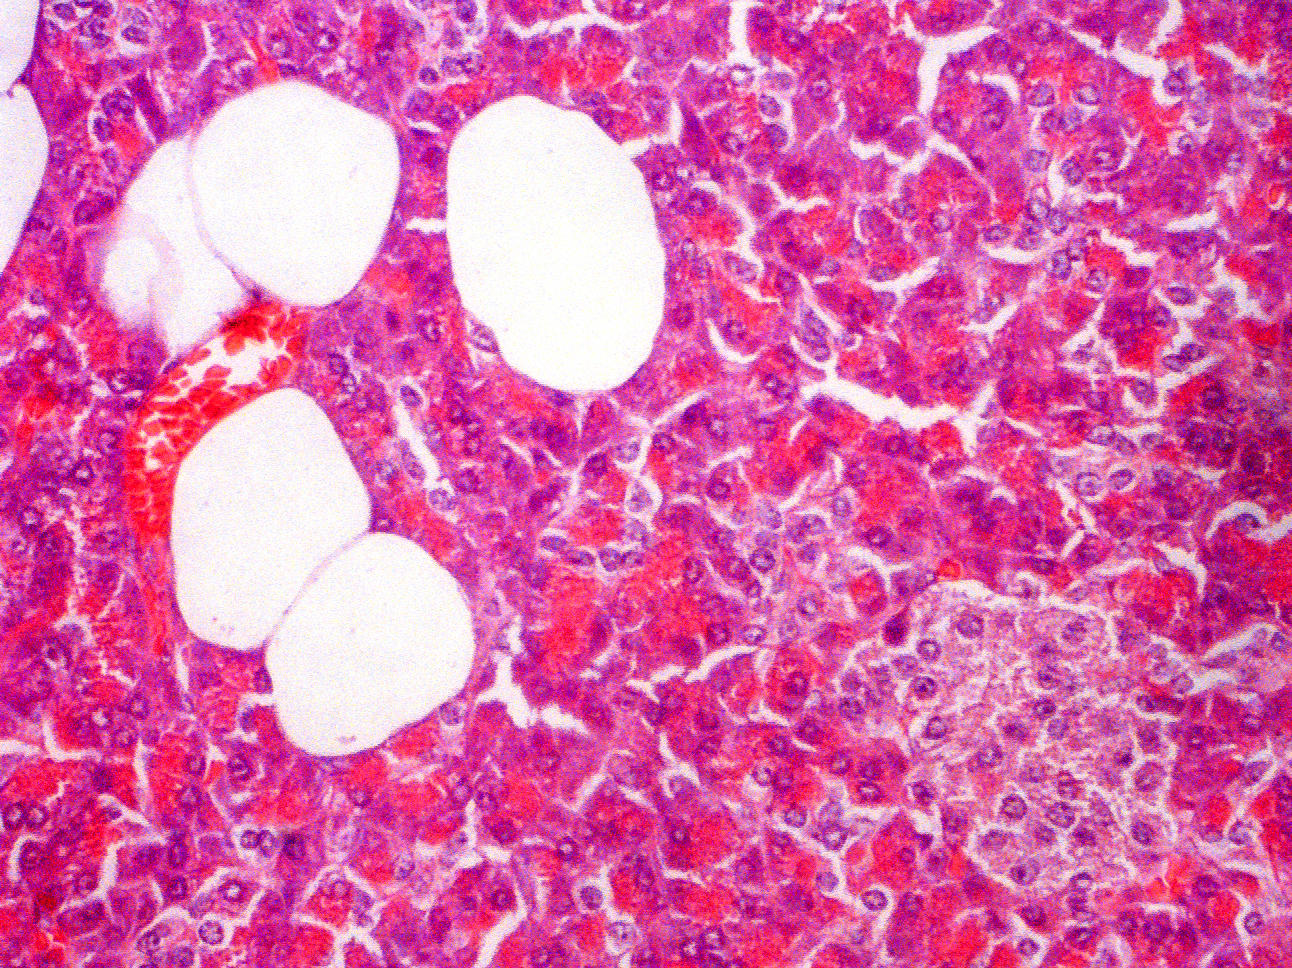

Small blood vessel vs Fat cells

A fat cell has a single nucleus placed eccentrically in the cell. No other nuclei are visible. No intimal layer is visible around the fat globule that comprises the bulk of the cell. Fat cells border each other or are directly in contact with surrounding tissues without the layers seen in blood vessels.